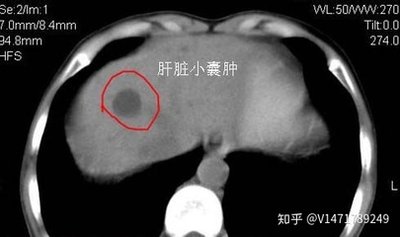

CT看到的肝囊肿

单纯性肝囊肿为先天性、非遗传性肝内囊性病变。囊腔通常不与肝内胆管系交通,囊肿是由上皮细胞排列组成的闭合腔隙,内含液体,可为单发性或多发性。本病属于肝囊肿的一种主要类型。一般认为本病是起源于肝内迷走胆管的一种滞留性囊肿,属于先天性发育异常。肝囊肿生长缓慢,多数病人无明显症状,仅在体检时被偶然发现。巨大的肝囊肿可出现明显的压迫症状。若合并感染,可出现畏寒、发热、腹痛等类似肝脓肿的症状。